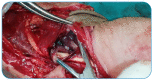

Hydatid Cyst in the Hand